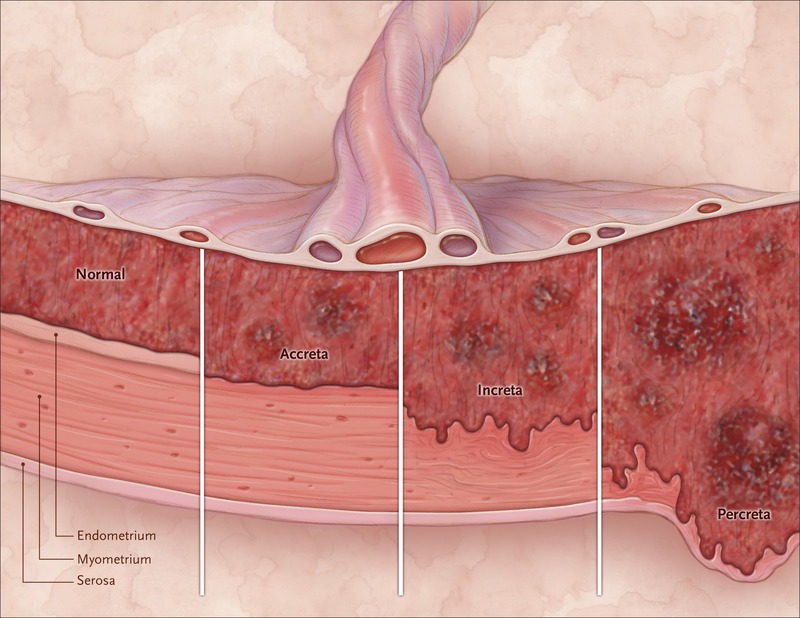

وتحدث هذه الحالة، التي تعرف باسم طيف المشيمة الملتصقة، عندما تلتصق المشيمة بعمق شديد بجدار الرحم ولا تنفصل بعد الولادة، مما يؤدي إلى نزيف حاد بعد الولادة وأحياناً إلى استئصال الرحم وحتى الوفاة.